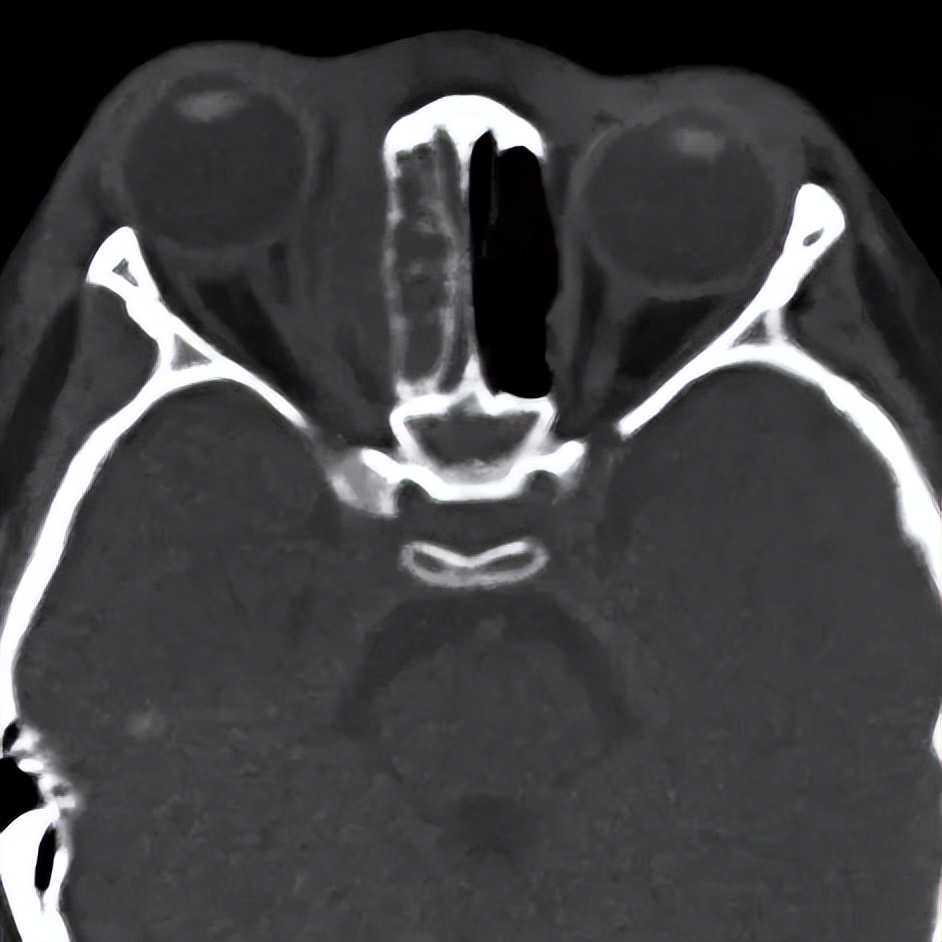

图 | 患儿的CT影像

根据患儿的CT表现,符合鼻窦炎的眶并发症,属于眼科和耳鼻喉科的急危重症。药剂科认为,目前患儿已经接受了经验性广谱抗生素的治疗,眼部红肿没有明显好转,病灶持续扩大,患儿仍有发热、食欲不振等严重感染的全身表现,考虑药物治疗效果差,目前脓肿已形成,需积极进行手术引流。

耳鼻喉科闫燕主任高度重视患儿病情,组织全科进行了病例讨论。考虑到患儿是3岁女童,眼部切口进行眶内脓肿引流对于患儿将来的面容存在影响,且术后眼部换药患儿难以配合,CT所见患儿炎症集中在眼眶内壁周围,可以尝试经鼻进行手术。马芙蓉教授阅片后发现, 患儿的眶内下角存在一个非常小的骨质不连续区域,可能是炎症从鼻窦向眼眶感染的通道,也是经鼻进行引流手术的关键突破口 。